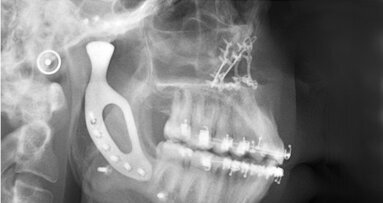

De door het Radboudumc ontwikkelde 3D-methode wordt sinds november 2014 gebruikt voor patiënten die een implantaatgedragen prothese voor de bovenkaak nodig hebben. Het begin van de behandeling voor het 3D-gebit is hetzelfde als voorheen: eerst wordt met bot uit de bekkenkam van de patiënt het versleten kaakbot weer opgebouwd, zodat er na zes maanden voldoende botvolume is. Tijdens de tweede operatie worden zes implantaten in de opgebouwde bovenkaak geplaatst, waarop direct de 3D-geprinte prothese wordt vastgeklikt.

Deze directe plaatsing is mogelijk doordat in het nieuwe 3D-lab tot op de tiende millimeter nauwkeurig een implantaatplanning kan worden gemaakt. Hierdoor is de plaatsing van de implantaten zekerder dan bij de ‘standaard’-planning. De 3D-printer kan de prothese vervolgens exact op maat printen, zodat deze in dezelfde sessie als de implantaten geplaatst worden.

Het resultaat: zes maanden tijdswinst en een veel grotere precisie en kwaliteit in de implantaatplaatsing. Uit de feedback van patiënten blijkt dat zij over de geprinte prothese zeer te spreken zijn. Naast de kortere behandeling ervaren zij ook meer zekerheid over het vastzitten van de prothese.